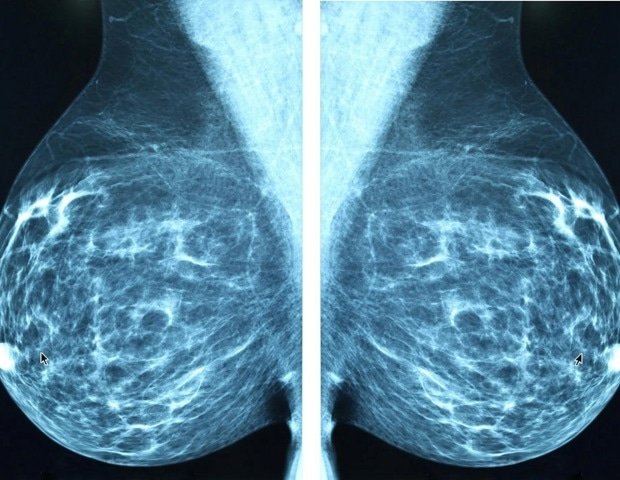

The research team discovered that FAM83H-AS1 is frequently amplified and is particularly active in tumor tissues. High levels of this RNA molecule are associated with reduced anti-tumor immunity and lower survival rates in breast cancer patients. The important thing is that they clarify how it works. Researchers reveal that FAM83H-AS1 hijacks a critical signaling pathway known as cGAS-STING. Rather than triggering a strong antitumor interferon response, high levels of FAM83H-AS1 shift pathway signaling toward a pro-neoplastic inflammatory response driven by NF-κB. This switch effectively disarms the body’s natural defenses, turning immune attacks into cancer-fueling inflammation.

Since overexpression of FAM83H-AS1 has been linked to poor prognosis in many cancers, the researchers believe that its immune evasion mechanism may not be limited to breast cancer. Their work also points directly to a therapeutic insight—tumors characterized by FAM83H-AS1 overexpression or subsequent NF-κB activation may be particularly vulnerable to checkpoint blockade therapy.